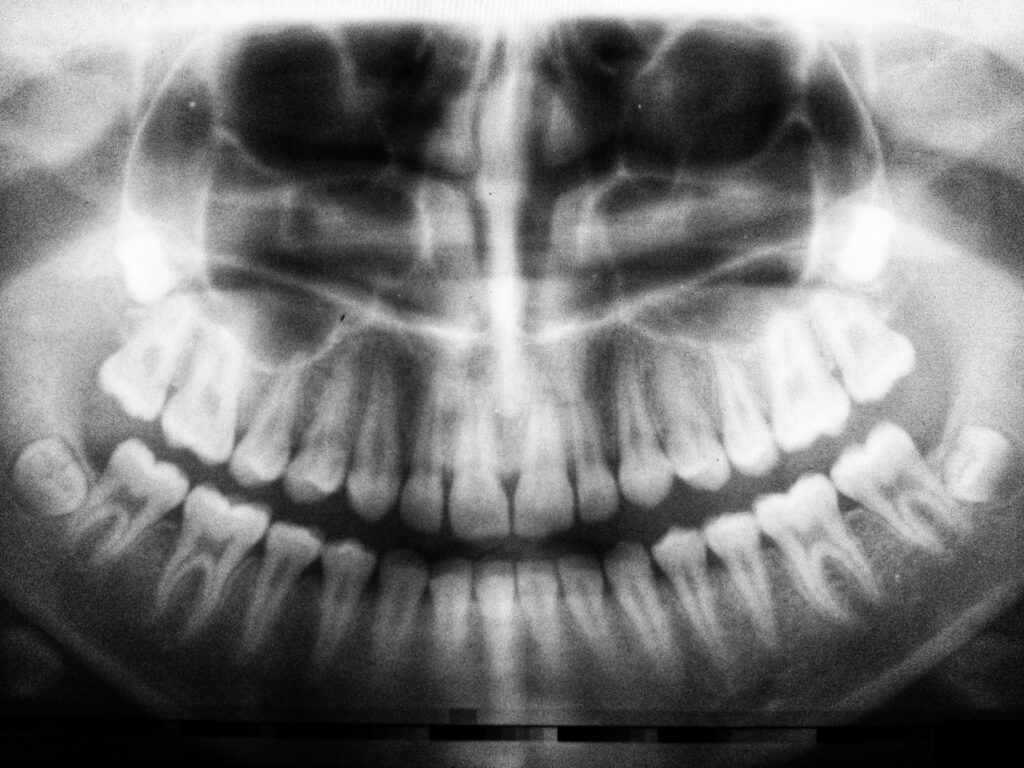

One of the procedures used in oral and dental health is the Panoramic X-ray. This X-ray procedure provides a pathological view of the teeth and jaw, and it allows even the smallest details of the formations in the upper and lower jaws to be easily observed.

In other words, with a single film capture, it provides the opportunity to see all the discomforts and the paths that need to be followed to address these discomforts. It should be taken after the initial examination to determine the treatment plan.

The reason panoramic dental X-rays are so widely preferred in modern dentistry is that, unlike standard X-rays, they capture the entire mouth in a single image.

This allows for the easy detection of a wide range of issues, from problems in the bone structure to gum infections.